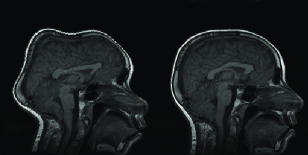

Images in the first row of Figure 4 shows a source and target images in image scale. In the second row on the same figure, the same slices are displayed after standardization using the parameters defined above.

Figure 4: images in non-standard(1st row) and standard scale(2nd row)

Refer to caption